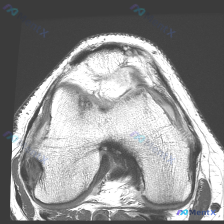

单张膝关节MRI看软骨异常?这里的坑很多人踩过

今天遇到一个有意思的读片问题:只给了一张膝关节轴位MRI,问这里有没有软骨异常,整理一下分析思路分享给大家。

提供的是膝关节单张轴位MRI扫描图像,可识别的解剖结构包括:前方的髌骨、中部的股骨内外侧髁与髁间窝、髌股关节间隙,以及周围部分软组织。

- 软骨结构:髌骨后方关节软骨面、股骨滑车软骨轮廓清晰,连续性尚可,这一轴位层面没有看到明确的软骨信号异常、全层缺损或者明显裂隙

- 骨性结构:髌骨、股骨内外髁皮质连续,没有看到明显骨折线、骨质破坏或者局灶性骨髓水肿信号,髌骨骨质信号也未见异常

- 关节与软组织:髌股关节间隙清晰,没有看到明显异常关节积液,显示范围内也没有看到软组织肿块或者异常水肿信号

从当前这张图像来看,此可见层面没有明确的软骨结构异常,髌骨和股骨滑车软骨的形态、信号都符合正常表现。